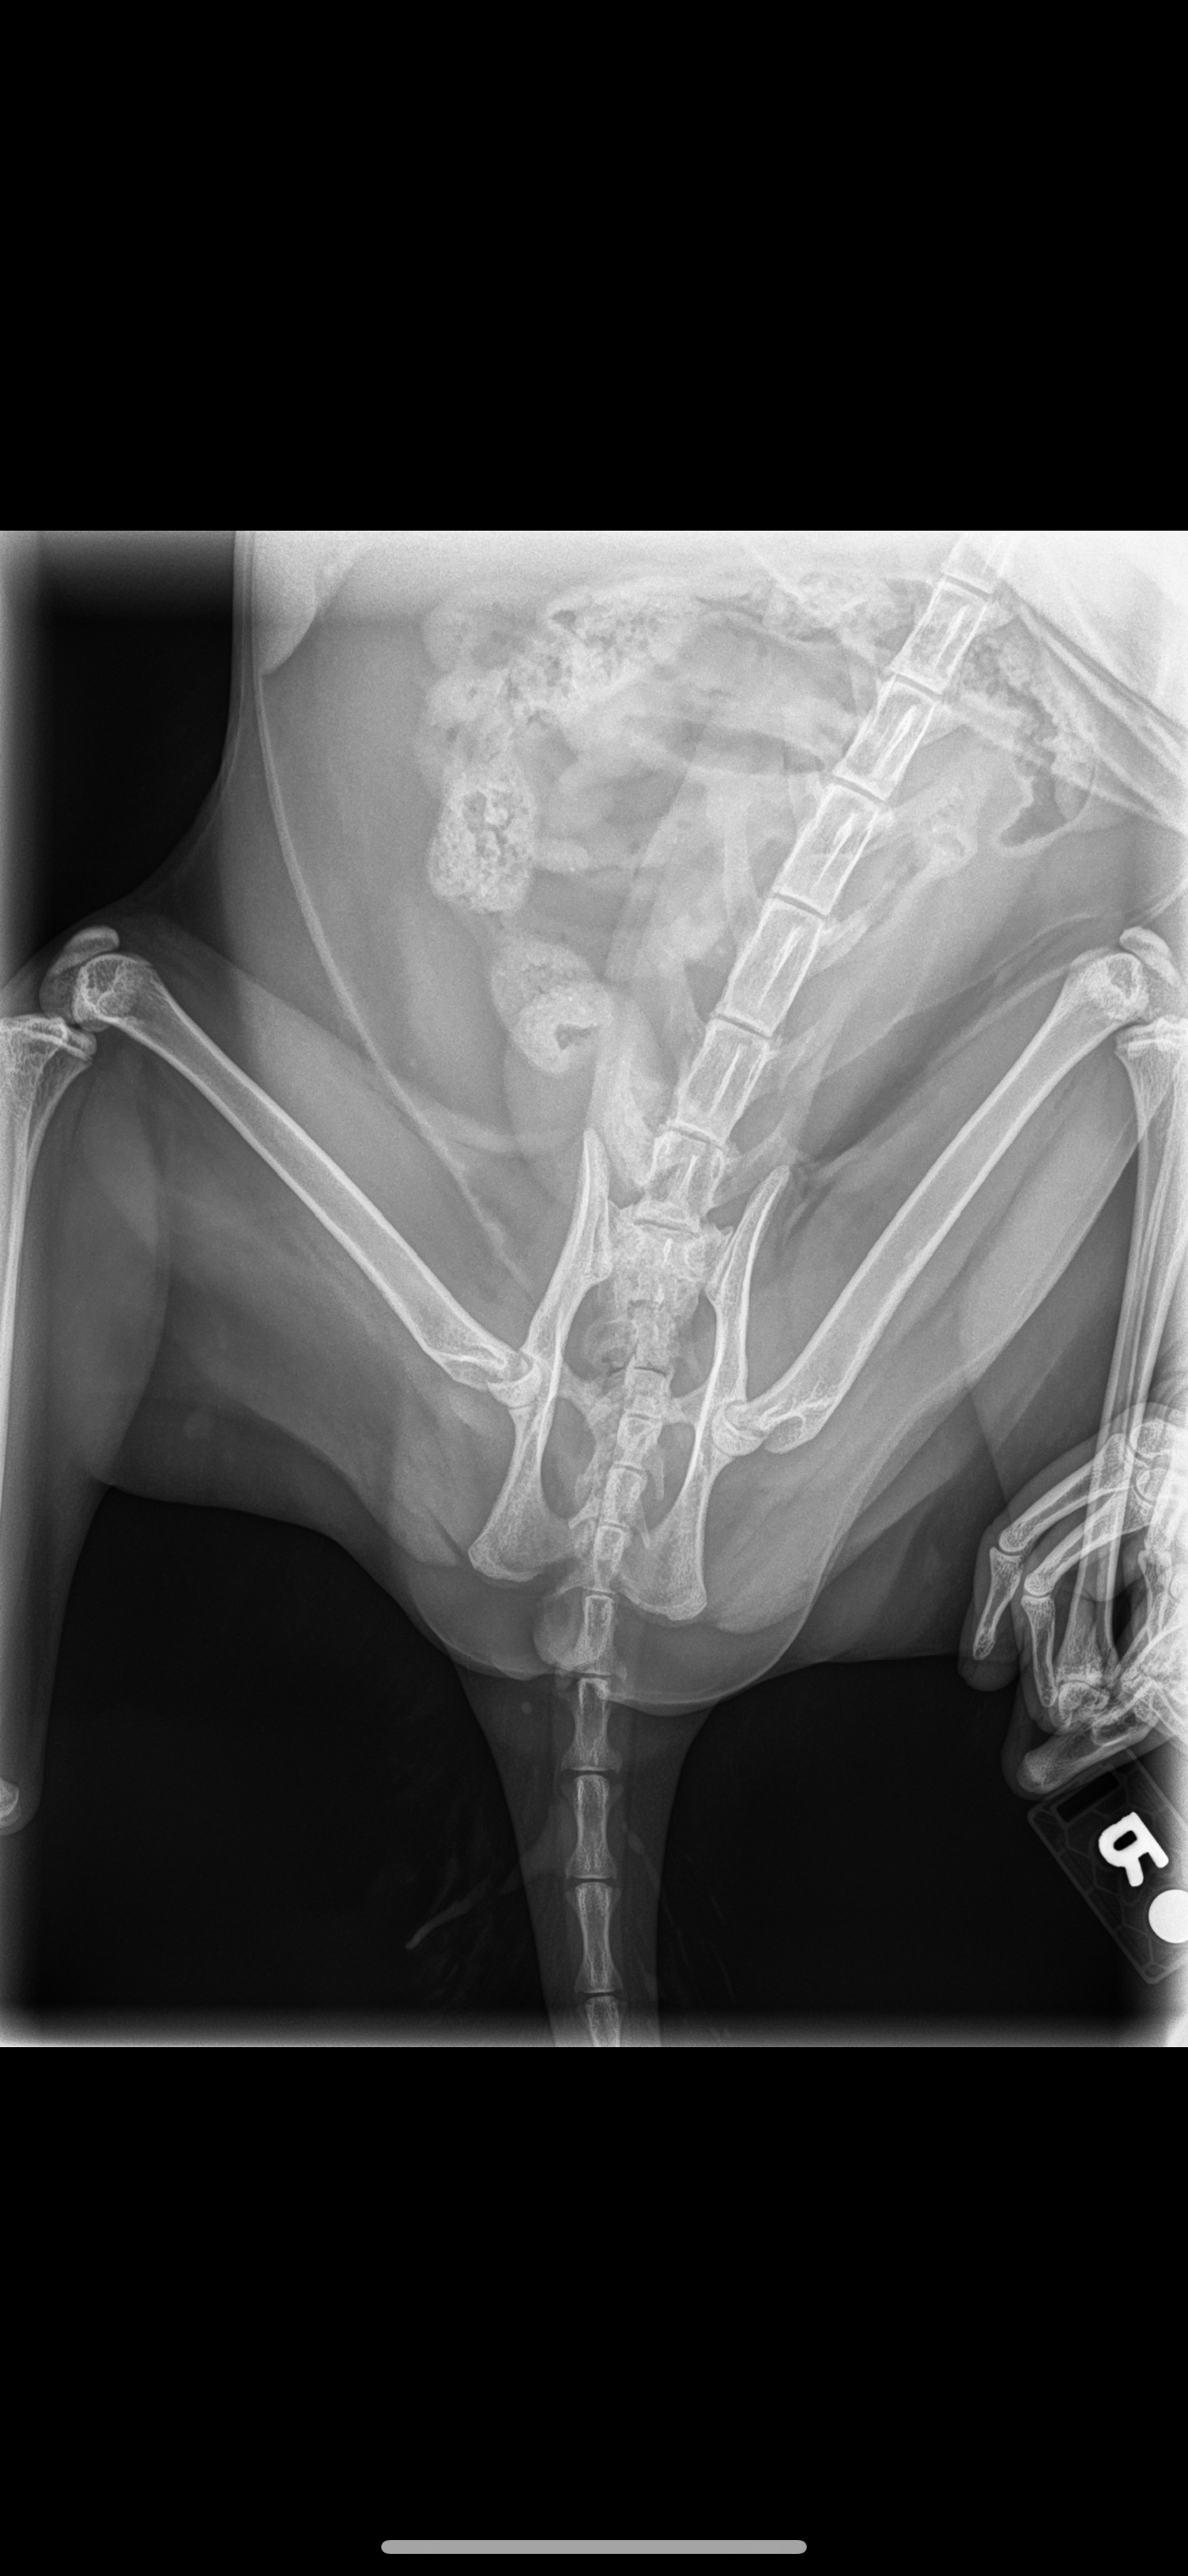

Hello, my name is Kristy and I’m making a GoFundMe for my daughter and her emotional support cat. Unfortunately, we got bad news yesterday after his eight-week checkup from his first hip surgery that he will need a second hip surgery for the right hip. So in order for us to be able to get it, we have to try to earn the money for his second surgery. We need to get the surgery done ASAP before the right hip breaks and he’s unable to walk again. If you could please find it in your hearts to help, we would greatly appreciate it.

Meatball is not even two years old. We’re trying to give him some quality of life. He is also my daughter’s emotional support cat who is very important to her.